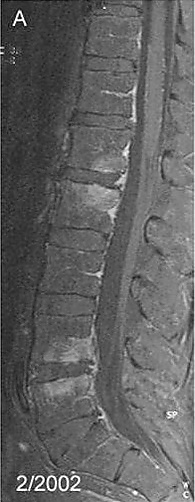

Спондилит — воспалительное заболевание позвоночника. Является одной из форм спондилопатии[3]. При спондилите происходит первичное разрушение тел позвонков, что приводит к деформации позвоночника.

Спондилит может быть специфическим, например туберкулез позвоночника, сифилитический, гонорейный и др., а также неспецифический: гематогенный гнойный спондилит, а также болезнь Бехтерева.